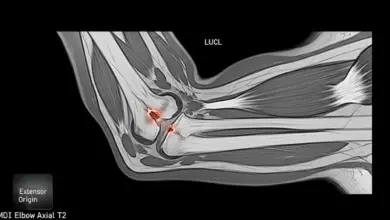

- A ressonância magnética detalha cartilagens, ligamentos e possíveis corpos livres.